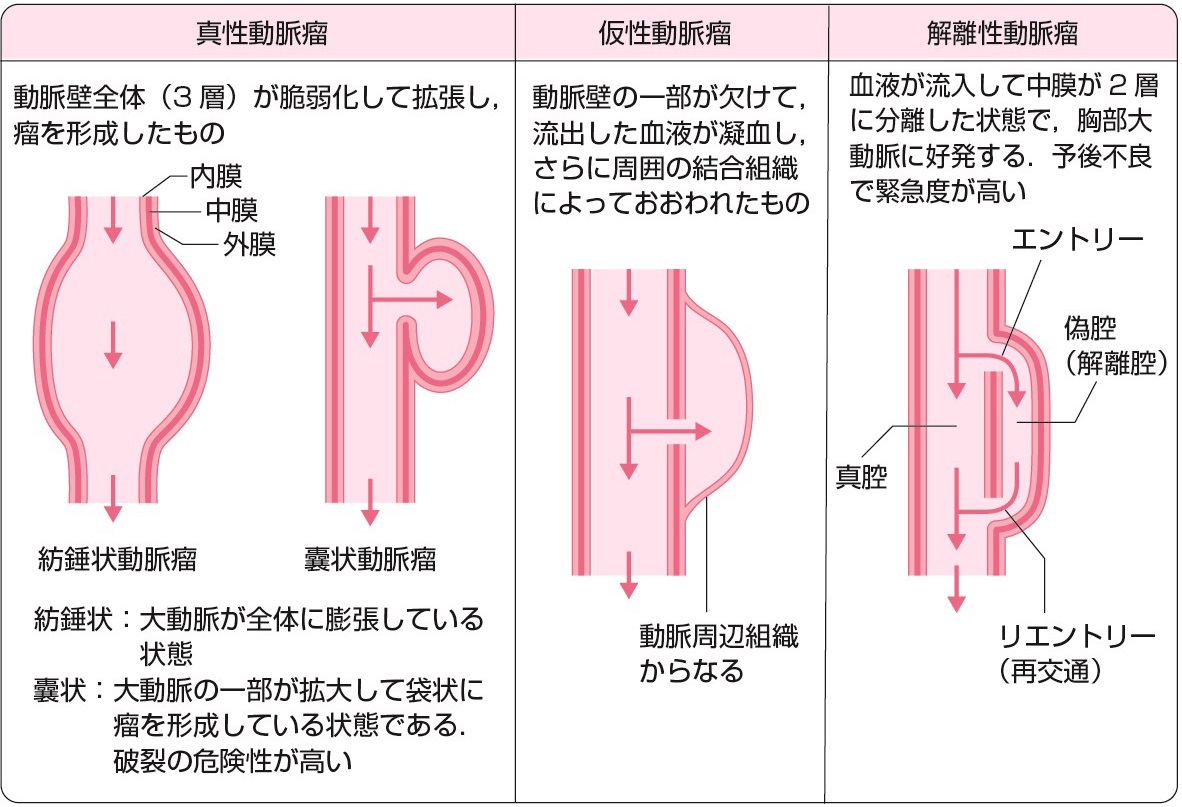

真性動脈瘤と仮性動脈瘤と解離性動脈瘤

大動脈壁が脆弱化して局所的に全周性または一部が拡張した状態を大動脈瘤とよぶ.一般に,大動脈の外径の直径が正常部位の1.5倍 (目安として胸部大動脈系45 mm,腹部大動脈30 mm) をこえた状態を大動脈瘤と定義する.大部分は無症状のままに経過し,健診や医療機関受診の際の視診や触診,胸部X線写真正面像における縦隔拡大や側面像における拡大,腹部触診や腹部超音波 (図2) やCT (図3),MRI (図4) で発見され診断される.瘤の形状によって,紡錘状あるいは囊状,また壁構造の違いによって,瘤が内膜・中膜・外膜の3層すべてを有する真性動脈瘤と,中膜平滑筋層の連続性が失われ外膜や結合組織によって被包されている仮性大動脈瘤に分類される (図5).大動脈壁脆弱化の原因としては,外傷,梅毒,Marfan症候群などもあるが,最も大きな割合を占めるのは高血圧と加齢に伴う動脈硬化性変化であり,高齢男性に多い.大動脈瘤が解離したり破裂したりすると,激烈な胸背部痛や腹痛を訴えたり,血圧低下しショックに陥ったりする.いったんショック状態に陥った症例はもちろんのこと,病院に搬送されたとしても救命できる可能性は50%以下とされる.瘤径拡大スピードが高いほど,瘤形状が全体的でなく部分的であるほど,また当然,血圧が高いほど破裂リスクは高い.